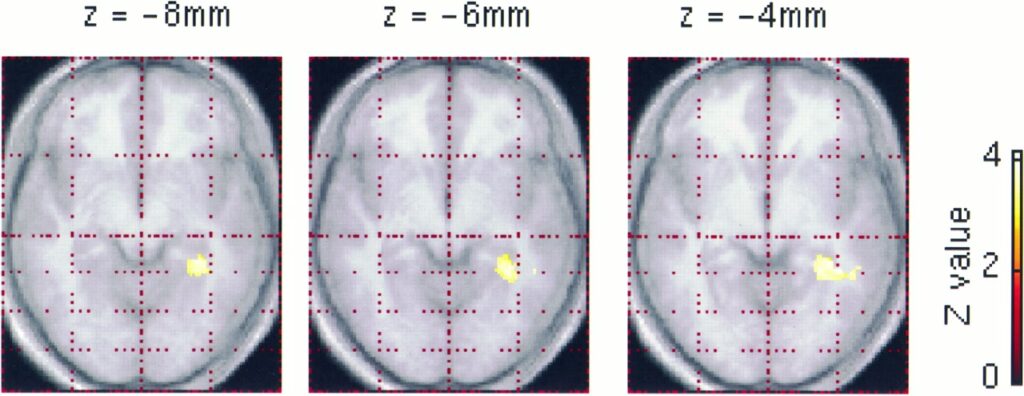

A significant study, utilising structural Magnetic Resonance Imaging (MRI) scans, compared the brains of licensed London taxi drivers with those of a control group of individuals who did not have extensive navigation experience. The aim was to identify any differences in brain structure that could be directly attributed to the unique demands of 'The Knowledge'.

- Voxel-Based Morphometry (VBM): This is an automated, objective technique that allows researchers to examine differences in brain structure at a very fine-grained level. VBM analyses the entire brain voxel by voxel (the 3D equivalent of pixels) to identify areas where gray matter density differs between groups. This method was used to get a broad overview of potential structural changes across the entire brain.

- Pixel-Counting Technique: For a more focused analysis, a manual pixel-counting method was used to precisely measure the volumes of specific regions within the hippocampus. This involved meticulously tracing the boundaries of the anterior, body, and posterior sections of the hippocampus on MRI scans. This method allowed for a detailed volumetric assessment of distinct hippocampal subregions.

The consistency of the results obtained from these two independent methods lent significant weight to the study's conclusions, confirming that the observed differences were robust and not an artifact of a single analytical approach.